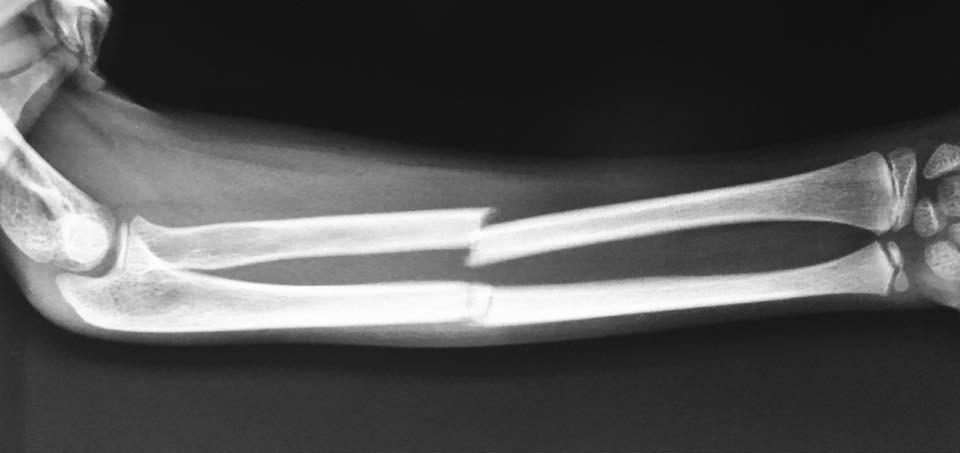

Fracture & Trauma Management

Rapid, effective treatment protocols to restore function and mobility following traumatic injuries and complex fractures.

Complex Reconstructive Limb Surgery

Expert surgical solutions for trauma, congenital deformities, and revision cases, restoring function and mobility to damaged limbs.